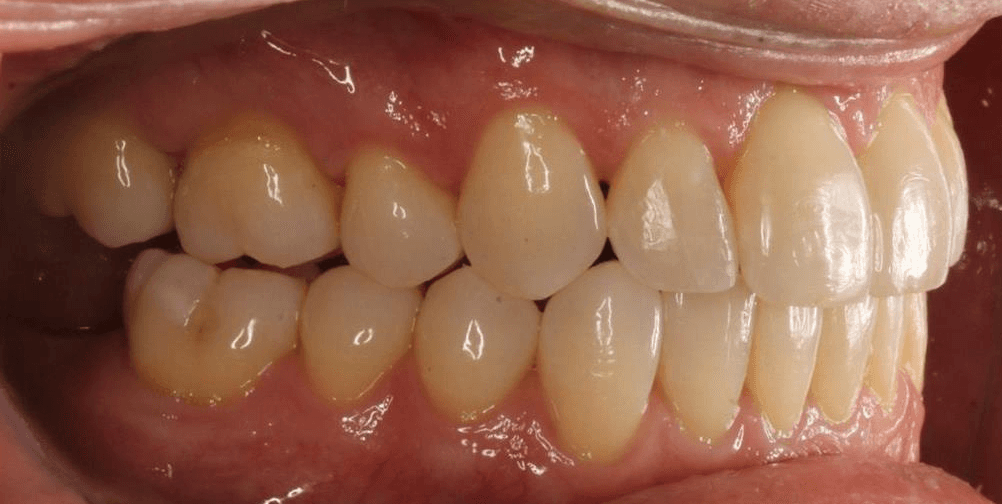

Initial treatment

INTRAORAL